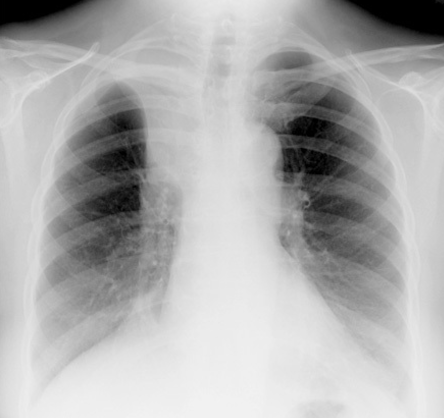

what does this show

sarcoidosis

BHL